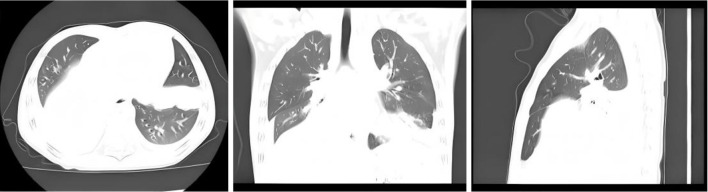

Methods: In this study, we conducted a retrospective study of 156 immunocompetent pediatric patients diagnosed with SAP, who were divided into the conventional treatments survivor group and death group, without receiving extracorporeal membrane oxygenation (ECMO). Baseline clinical features, laboratory data, imaging findings, treatments and complications were collected. Patients were followed until discharge or death, with mortality confirmed from medical records.

Results: There were 156 children included, with 142 patients in the survivor group and 14 patients in the death group. The mean age was 30.12±28.78 months, with no significant differences in age or sex between the survivor group and the death group (P>0.05). In univariate analysis, significant differences were observed in shortness of breath, tachycardia, low oxygen saturation (SpO2), partial pressure of oxygen (PO2), partial pressure of carbon dioxide (PCO2), and pulmonary consolidation involving two or more lobes and so on (all P<0.05). Respiratory failure, septic shock, and acute respiratory distress syndrome (ARDS) were significantly more common in the death group (P<0.05). In the multivariate analysis, the independent risk factors for death included decreased SpO2 [odds ratio (OR): 32.336, 95% confidence interval (CI): 2.385-619.473, P=0.02], increased pressure of carbon dioxide in arterial blood (PaCO2) (OR: 2.187, 95% CI: 1.079-4.434, P=0.03), and pulmonary consolidation affecting two or more lobes (OR: 9.071, 95% CI: 1.123-73.248, P=0.04).

Conclusions: These findings emphasize the importance of close monitoring of SpO2, PaCO2 levels, and extent of lung consolidation in children with SAP undergoing conventional treatment. Recognizing these risk factors early may prompt consideration of advanced supportive therapies beyond conventional measures to improve survival outcomes.